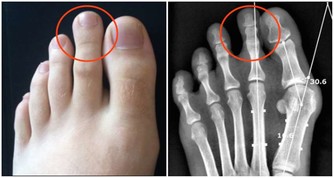

- 頸椎病變:長時間伏案工作容易造成頸椎退化或椎間盤突出,進而壓迫神經根,導致手部麻木。

- 腕管綜合症:反覆使用手腕或長期握持物品可能引發腕管內神經受壓,出現手部麻木及刺痛感。

保持正確的姿勢與適時休息是預防神經受壓的重要措施。